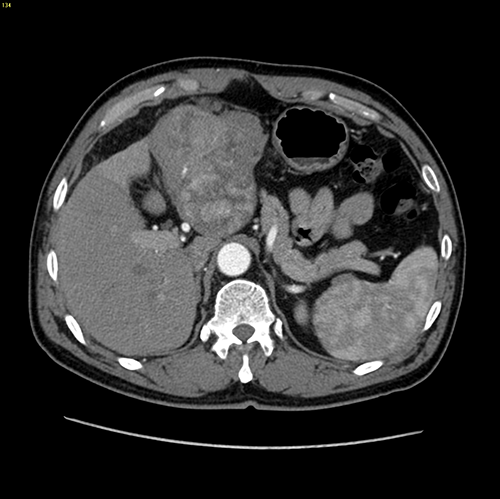

左肝癌、门静脉癌栓---左半肝切除